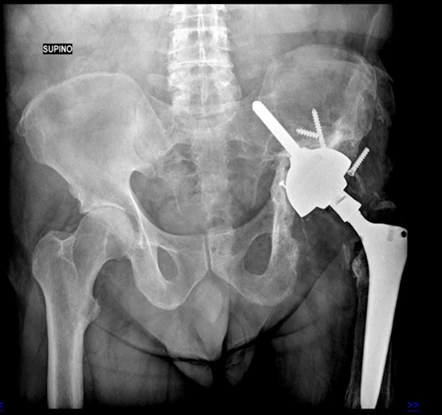

A tale proposito ho sviluppato in collaborazione con Medacta, nota e azienda Svizzera molto attiva in campo ortopedico e aperta alle innovazioni tecnologiche, un nuovo impianto specifico per la chirurgia di revisione acetabolare progettato per affrontare i casi più complessi di difetto osseo sfruttando per la stabilità meccanica l’osso iliaco.

Caratteristiche distintive del cotile Mpact Ilac Screw e perché viene scelto in casi difficili:

1. Design e Modularità

È un sistema non cementato che punta sulla stabilità meccanica immediata e sulla rigenerazione biologica a lungo termine:

- Forma emisferica: consente la correzione di inclinazione ed antiversione

- Vite Polare: è l’innovazione tecnologica peculiare che consente di massimizzare la stabilità primaria ancorandosi saldamente entro l’osso iliaco solitamente presente anche nei casi più gravi di difetto osseo.

2. Indicazioni Specifiche

Il Cotile Mpact Ilac Screw viene impiegato quando il normale “alloggio” dell’anca è compromesso da:

- Mobilizzazione della vecchia protesi che ha “scavato” o distrutto parte del bacino.

- Difetti ossei gravi (classificati come Paprosky II o III) e disgiunzione pelvica

- Esiti di traumi complessi o displasie congenite che alterano l’anatomia standard.

3. Stabilità iliaca

- Concetto vecchio, disegno moderna: La vite iliaca funge da vero e proprio “pilastro”, trasferendo il carico meccanico direttamente nella colonna posteriore/superiore del bacino, entro l’osso iliaco, bypassando le zone di osteolisi e il difetto cavitario/segmentario dell’acetabolo.

In sintesi, il cotile Mpact Ilac Screw è un cotile innovativo che permette di “ricostruire” l’articolazione anche in presenza di ampi difetti ossei evitando il ricorso a protesi custom-made o altri impianti molto più complessi e costosi.